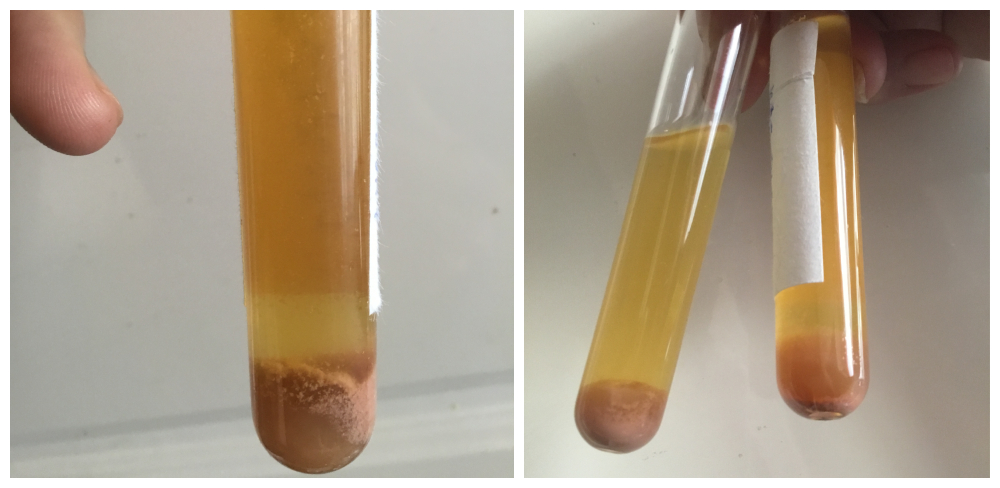

Rohantunk Budapestre a vizeletmintával, leadni a Semmelweis laborba. Az eredmény sokkoló lett:

A vizeletet Dr Ledó Nóra eredetileg a portára (!) akarta velünk leadatni. Nem tudom, hallott-e már valaki ilyet?! Persze a laborba vittük és megvártuk míg adminisztrálják, hogy biztos ne történjen olyan véletlen, hogy eltűnik. Ezután siettünk magánúton (abszurdum) szívultrahangra, ahol 29 ezer forintot fizettünk ki a cégnek, mert Dr. Ledó azt mondta a komoly baloldali mellkasi-szívtáji és lapockatáji-háti fájdalommal küzdő fiamnak – ami tünetek egyszerre jelentek meg a vérvizeléssel, vesefájdalommal, magas pulzussal – hogy „Nem tudom elintézni, a klinikán 4-5 hetet kell várni egy szív ultrahangra”. Teljesen gúnyt űzött az orvosnő a fiam súlyos állapotából. Ekkor be kellett volna menni az igazgatóhoz, hogy egy SOTE Belklinika hogyan teheti ezt meg akut betegekkel? Talán ha felvette volna a borzalmas állapotú fiamat a kórházba, egy napon belül is megtörténhetett volna TB-finanszírozottan. Visszatérve az eredményre, a vizelet 10 pozitív eltérést mutatott, mivel nehéz lehet az apróbetűket olvasni, az alábbiakban leírva is közlöm:

– 2 keresztes fehérjevizelést

– 3 keresztes vérvizelést

– vörösvértestek zsúfolva/látótér! (egy másik ottani nefrológus azt mondta, 10-15 vvt/látótér értékekkel találkozik a napi gyakorlatban – Zsoltnak 100 és 1000-szerese volt ennek, ismét!)

– fehérvérsejt (genny) 10/látótér (ref. érték: 2) – ezúttal már genny is volt a vizeletben, amit a doktornő gátlástalanul letagadott nekem

– baktériumok sok/látótér

– Calcium-oxalát kristályok sok/látótér.

– Albumin a vizeletben több mint 3-szorosa

– Összfehérje a vizeletben több mint 7-szerese (a vese átengedi a fehérjét!)

– Kreatinin a vizeletben 3-szorosa a normális értékek felső határának.

Visszatérve a mintákra, párhuzamosan leadtunk egy mintát a Synlab-hoz is, kvantifikálja az eredményt ellentétben más leletekkel. Szintén alarm eredmény!